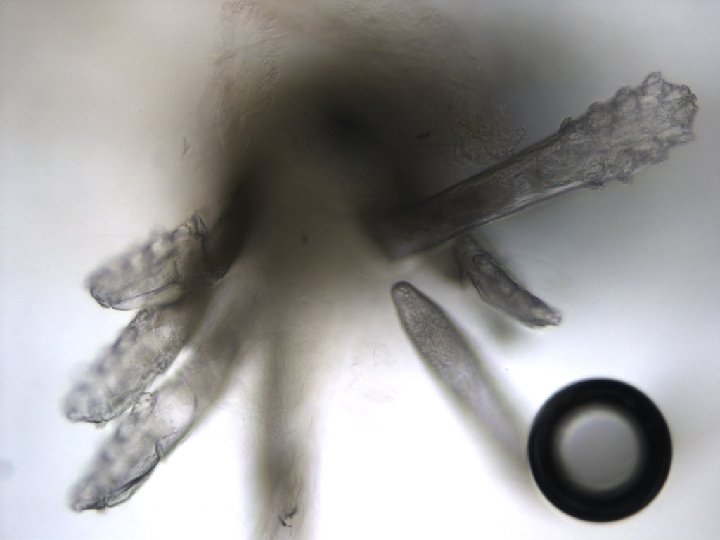

Demodex folicorum